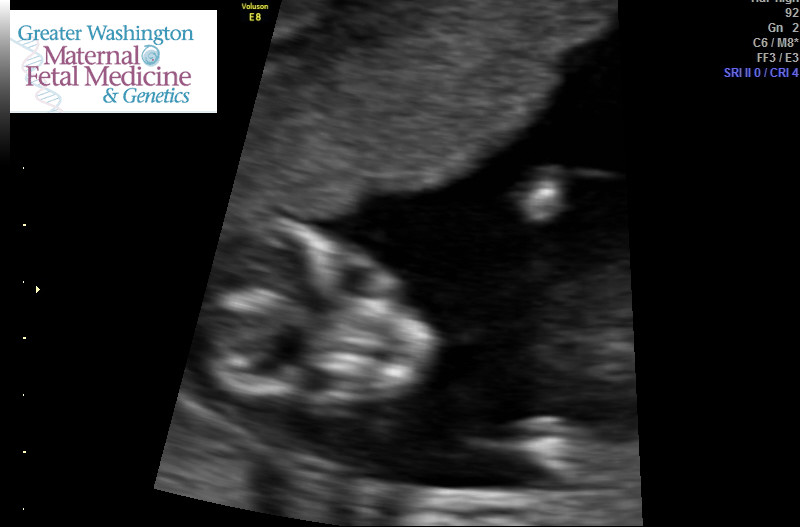

We had a scan on the 11th for a large cyst on my ovary was 13w 1d and husband asked about gender she said super early but could let us know what she thought it might be this is what she showed us.... husband is set that it is was it show but I feel it's super early and that's really really big since it shows half the size of its thigh (see profile pic it won't let me post)